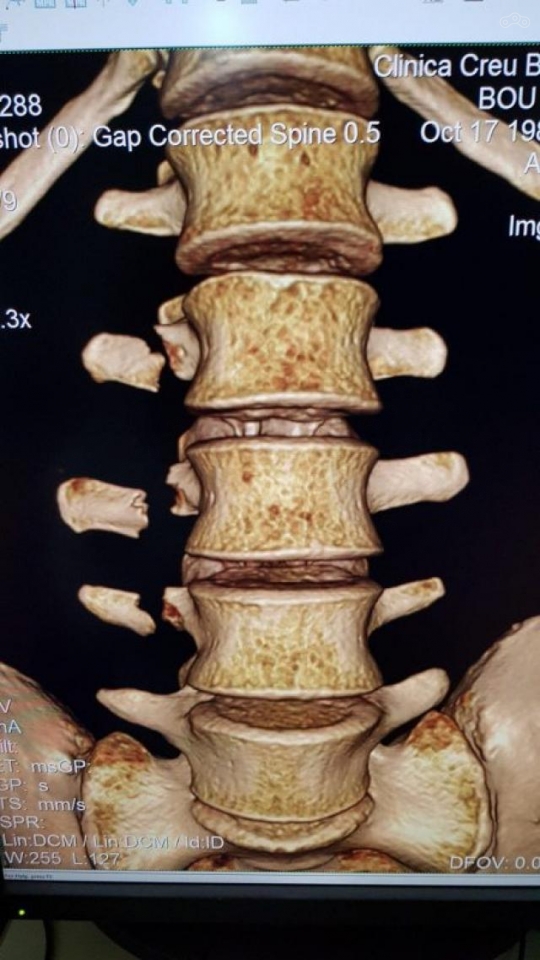

Тони Боу повредил три позвонка на чемпионате X-Trial

Врачи диагностировали у 31-летнего спортсмена переломы трёх позвонков и посоветовали воздержаться от нагрузок в ближайшие несколько недель. Скорее всего, испанец пропустит следующий этап, который запланирован на 8 марта в Испании.